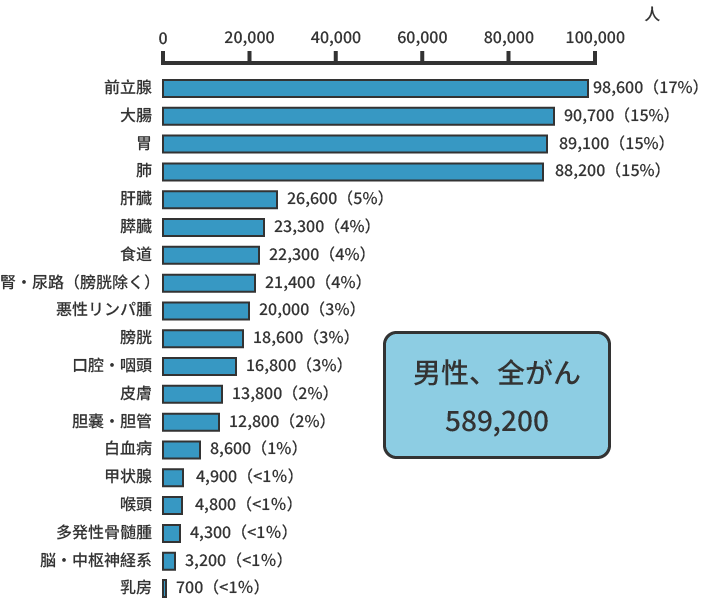

2021年の推計値では、日本のがん患者数は、約100万9,800人(男性約57万7,900人、女性約43万1,900人)です。部位別でみると、男性では前立腺がん(17%)、胃がん(16%)、大腸がん(15%)、肺がん(15%)、肝臓がん(5%)の順で多く、女性では乳がん(22%)、大腸がん(16%)、肺がん(10%)、胃がん(9%)、子宮がん(7%)の順で多くなっています。

部位別予測がん罹患数(2021年)